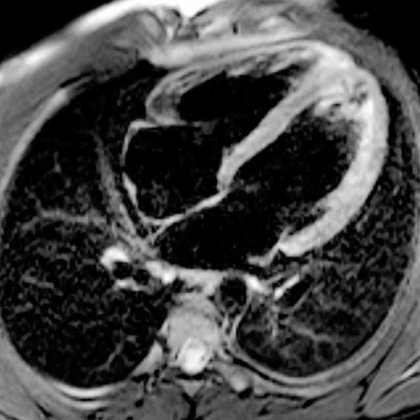

Shedding light on the drivers of rare myocarditis after mRNA SARS-CoV-2 vaccination. An important step towards fully realizing the tremendous potential of mRNA vaccines. Our latest paper published today in @SciImmunology. A summary: (1/11) https://t.co/jzuTBdc8q2

Cytokine-driven killer lymphocytes and inflammatory monocytes characterize myopericarditis after SARS-CoV-2 mRNA vaccination.